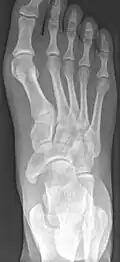

Radiological images

-

From left to right: Type 1, 2 and 3 -